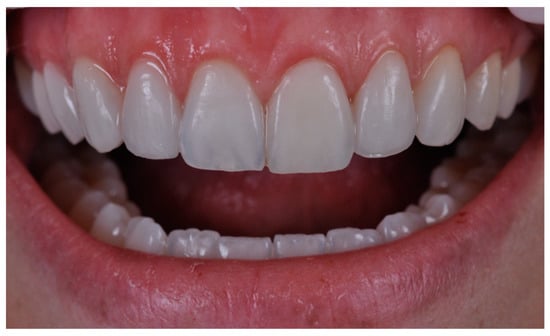

2. Case Presentation